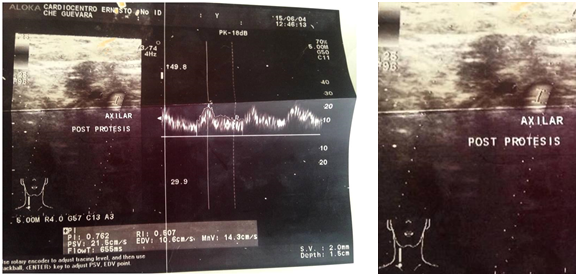

Volver a los detalles del artículo Aneurisma de la arteria subclavia izquierda